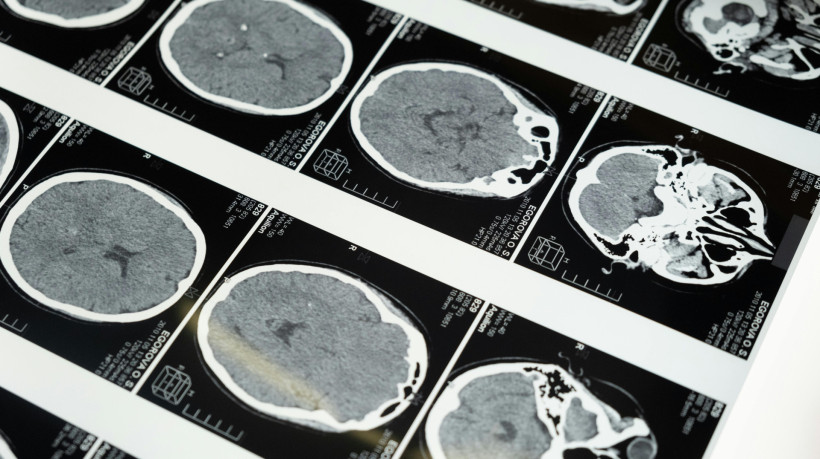

As Encefalopatias Espongiformes Transmissíveis (EET) são doenças neurodegenerativas que acometem toda a estrutura do Sistema Nervoso Central (SNC) tanto em humanos quanto em animais, como bois.

A DCJ é uma doença neurodegenerativa, caracterizada por provocar uma desordem cerebral com perda de memória e tremores. É de rápida evolução, e de forma inevitável, leva à morte do paciente.